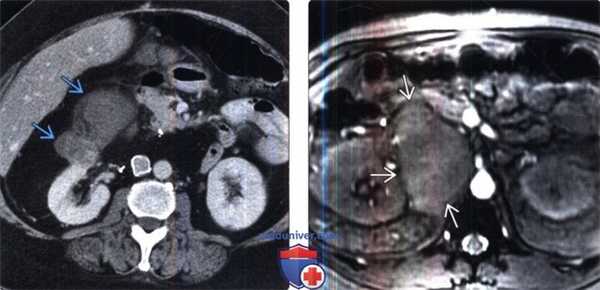

(Слева) КТ с контрастированием, аксиальная проекция: визуализирован двусторонний гидронефроз вследствие слившихся узловых метастазов забрюшинного пространства, ставших причиной мочеточниковой обструкции.

(Справа) КТ с контрастированием, аксиальная проекция: слившиеся узлы, окружающие чревный ствол, вследствие метастазирования рака пищевода. Рак дистального отдела пищевода часто метастазирует в верхние лимфатические узлы брюшной полости, печень или легкие.